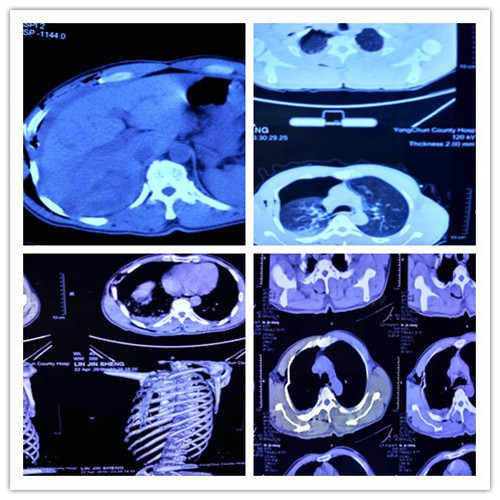

近日,我院普外科成功救治一位肝破裂患者。患者林xx,男性,57岁,以“摔伤致胸腹部疼痛约1日”为主诉转入我院普外科。缘于患者骑车不慎摔伤,右侧肢体着地,即感右胸腹疼痛,伤后急诊入住当地县医院,行胸腹CT检查后示:右侧...[详细]